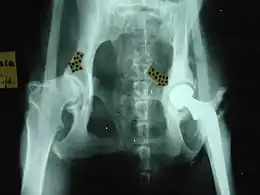

Orthopedic surgery

Common orthopedic surgeries in animals include:

- Ruptured cranial cruciate ligament repair

- For hip dysplasia:

- Femoral head osteotomy

- Triple pelvic osteotomy

- Hip replacement